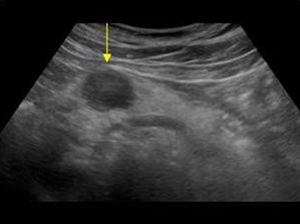

Con el transductor convexo, en epigastrio, realizaremos cortes transversales, longitudinales y oblicuos. Con la sonda en disposición transversal a nivel de epigastrio conseguimos un corte longitudinal del páncreas (fig. 9). Ventralmente o en superficie al páncreas nos encontramos con el lóbulo hepático izquierdo haciendo de ventana acústica. Dorsalmente o en profundidad con respecto al páncreas se sitúan la confluencia esplenoportal, la vena esplénica, la arteria mesentérica superior y la aorta, entre las que discurre la vena renal izquierda que desemboca en la cava.

Con la sonda en disposición longitudinal a nivel de epigastrio conseguimos un corte transversal del páncreas (fig. 10). Ventralmente o en superficie al páncreas nos encontramos con el lóbulo hepático izquierdo y el estómago con contenido líquido. Dorsalmente o en profundidad con respecto al páncreas se sitúan la arteria mesentérica superior y la aorta, entre las que discurre la vena renal izquierda.